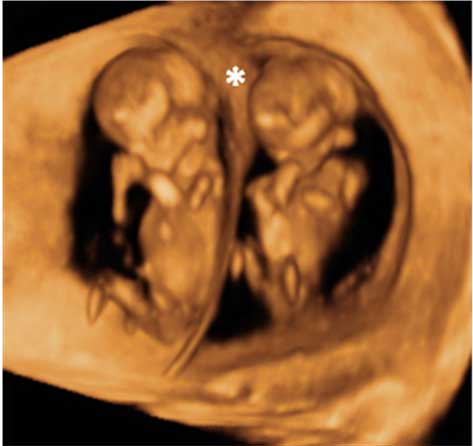

La ecografía en 3D de un embarazo gemelar muestra como los dos fetos crecen cada uno en una bolsa amniótica distinta, con su propia placenta. Los embarazos múltiples suelen conllevar más complicaciones que los embarazos únicos.

Gemelos de 12 semanas

La membrana de separación es claramente visible, más en la parte superior, donde se aprecia una cuña de tejido placentario (*). Esto indica que existen dos bolsas y dos placentas, la mejor situación para un embarazo gemelar. Cuantos más elementos comparten, más complicaciones puede tener la gestación.